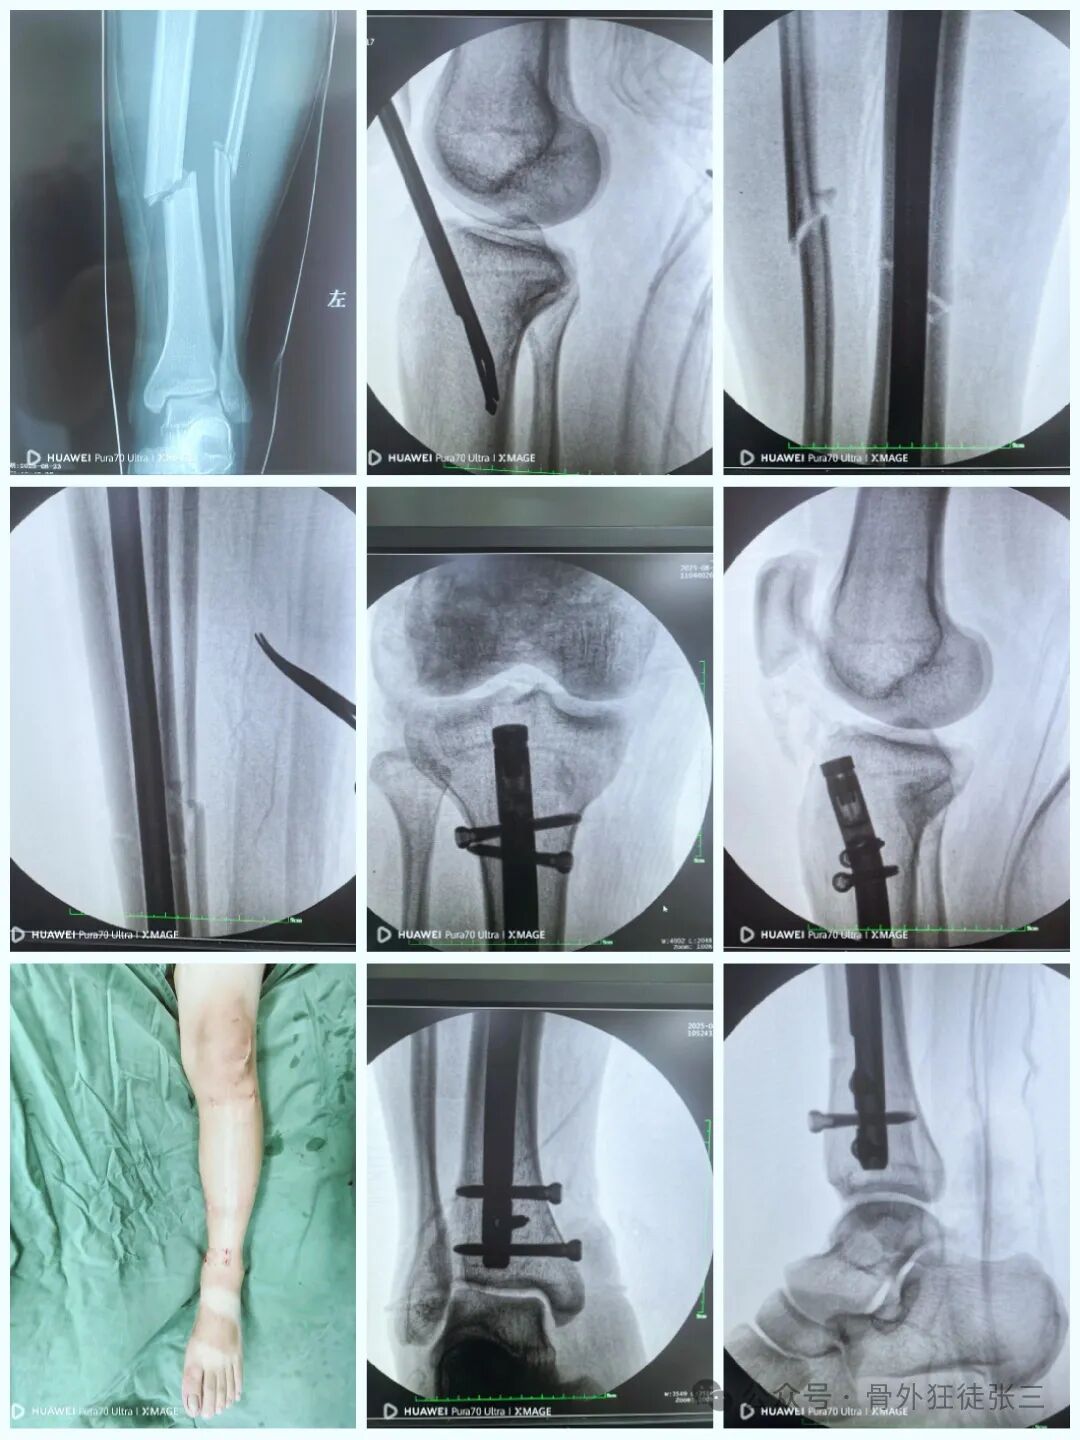

近年来,髌旁外侧入路髓内钉技术因复位精准、创伤小、康复快等特点,得到了广泛的应用。本文将围绕一例胫腓骨骨折案例,详细介绍该手术过程,为临床同仁提供思路与参考。

33岁,车祸伤追尾大车

胫腓骨骨折

患者无法接受消肿后手术

要求急诊手术

33岁,骨质特别硬

外观仅仅几个小口,超减张美容缝合

如何避免进针点偏外的处理

毕业外观照